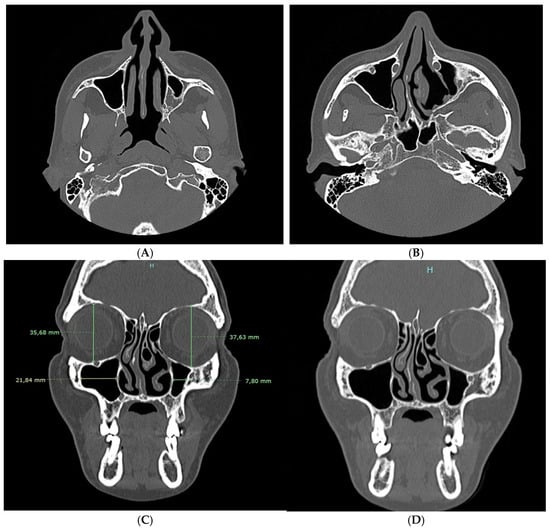

2. Case Report